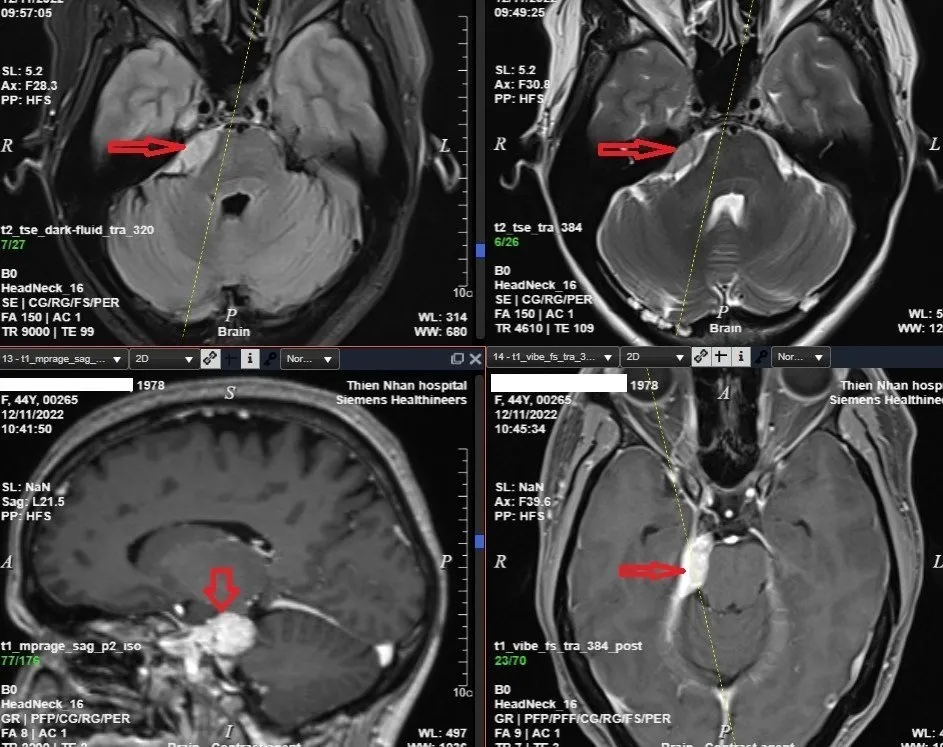

Hình ảnh chụp MRI não có tiêm thuốc đối quang từ của chị N cho thấy rõ u màng não

Gần đây, chị P.T.M.N (44 tuổi, trú tại Quảng Ngãi) đến Thiện Nhân Đà Nẵng khám sức khỏe định kỳ do công ty tổ chức. Khi chụp MRI não, mạch não trên hệ thống máy cộng hưởng từ MRI 3.0 Tesla Lumina - Siemens, phát hiện chị N có khối u màng não góc cầu tiểu não phải.

Chị N cho biết mình thường xuyên đau đầu, chóng mặt, được chẩn đoán rối loạn tiền đình và uống thuốc nhưng không khỏi. Với trường hợp của chị N, các bác sĩ tại Thiện Nhân Đà Nẵng đã tư vấn chị N đến khoa Ngoại thần kinh (Bệnh viện Chợ Rẫy TPHCM) và bệnh viện K Trung ương (Hà Nội) để tiếp tục thăm khám và điều trị.